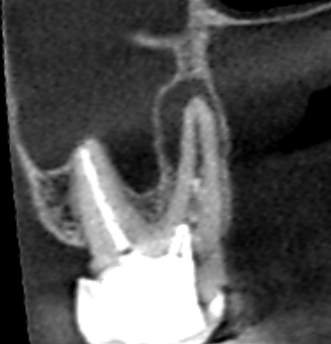

初診時の上顎第二大臼歯の矢状断のCT画像です。

赤い矢印の先に口蓋根をとり巻くような長い膿の影がみられます。歯根破折やと根尖孔外感染が疑われます。